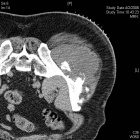

54 year old male with two year history of increasing swelling in left flank

Zoom image: Radiological image Radiological image.